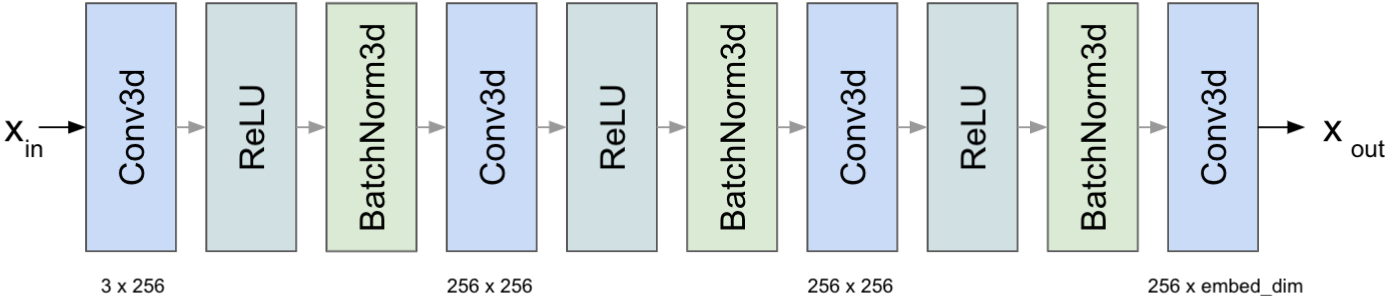

2.4 MLP for Positional Encoding

In TransBTS the learnable position embeddings, which introduce the location information, have fixed size. This results in limited input shape for inference since test images can not deviate in scale from the trained set if positional code is fixed. To address this issue we include a data-driven positional encoding (PE) module in form of Multilayer Perceptron (MLP). By directly using a 3D Convolution 1x1 we eliminate the problem with fixed resolution and add extra learnable parameters useful for positional embeddings. The MLP architecture consists of three consecutive blocks, where a single block has 3d convolution, relu activation followed by batch norm. This operation is formulated as follows:

where MLP block is displayed in Figure 3.